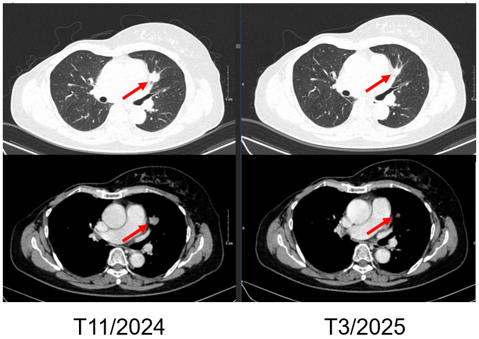

SO SÁNH TRƯỚC VÀ SAU ĐIỀU TRỊ

Hình 4. Hình ảnh chụp CT ngực trước và sau điều trị: Tổn thương tái phát thành ngực

Hình 5. Hình ảnh chụp CT ngực trước và sau điều trị: Tổn thương phổi trái

Hình 6. Hình ảnh chụp CT ngực trước và sau điều trị: Tổn thương phổi phải

- Chụp cắt lớp vi tính ngực:

+ Thành ngực phải có nốt đặc đường kính 5mm – theo dõi tổn thương tái phát

Phổi phải: nhu mô thuỳ giữa và dưới có các khối – nốt đặc, lớn nhất 7x8mm

+ Phổi trái: nhu mô thuỳ trên và đáy phổi sát màng phổi có các khối nốt đặc, lớn nhất 9x8mm